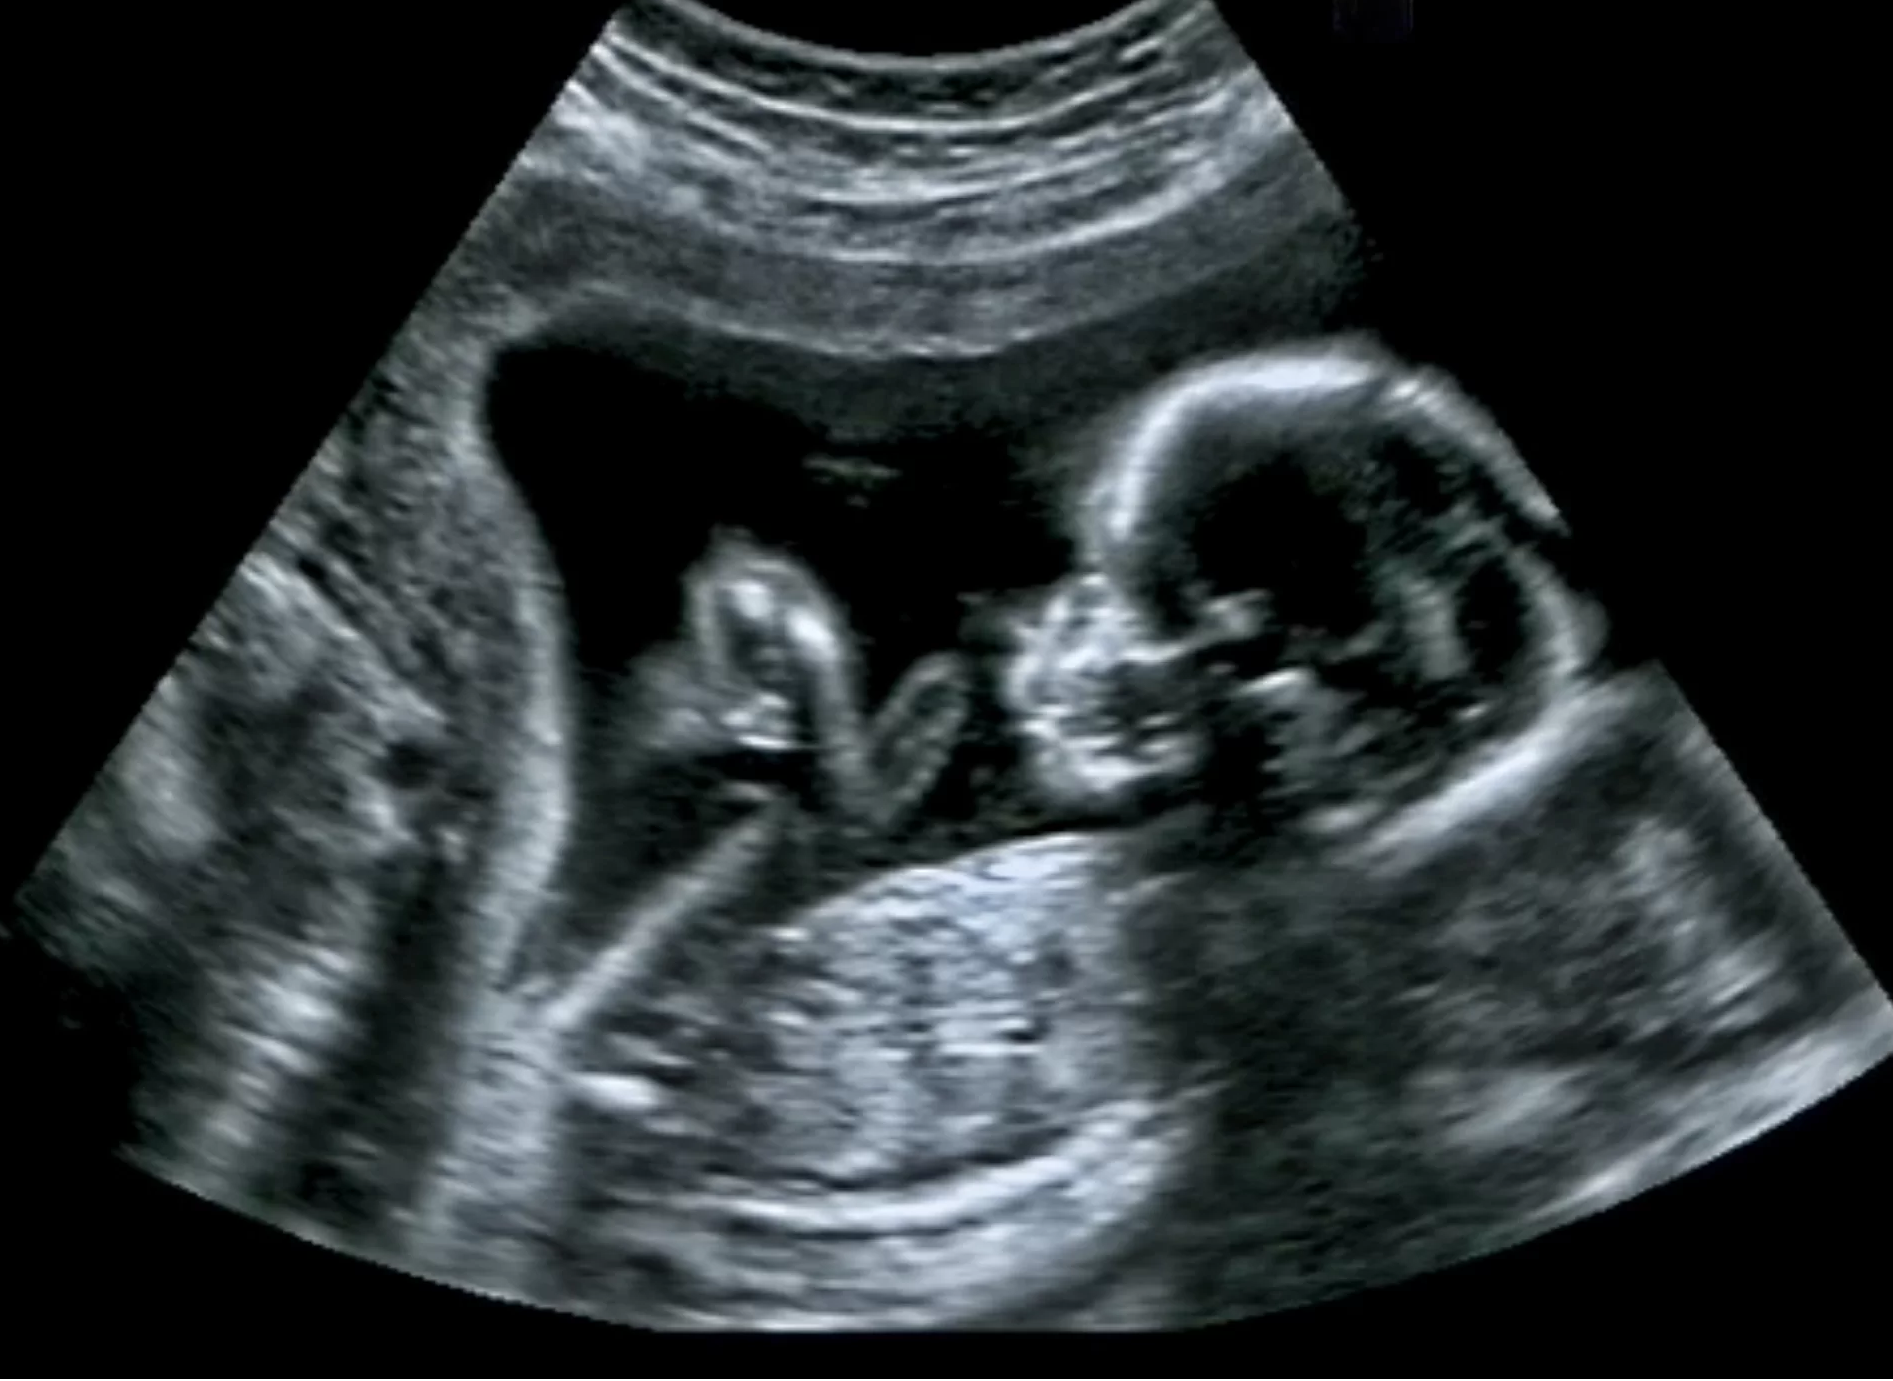

ช่วงเวลาที่น่าตื่นเต้นที่สุดระหว่างตั้งครรภ์ จะเป็นช่วงไหนไปไม่ได้นอกจากตอนที่แม่รู้สึกถึงการดิ้นของลูกเป็นครั้งแรก แต่คุณรู้หรือไม่ว่าจริง ๆ แล้วเวลาที่แม่รู้สึกว่าลูกกำลังเตะท้อง นั่นอาจสื่ออะไรได้มากกว่าที่คุณคิด

แต่ปัญหาคือ เราไม่สามารถวัดคลื่นสมองของเด็กในขณะที่พวกเขายังอยู่ในครรภ์ได้ ดังนั้น Fabrizi จึงได้ออกแบบการทดลองร่วมกับโรงพยาบาลมหาวิทยาลัยในลอนดอน เพื่อทำการศึกษาทารกแรกเกิด ทั้งคลอดก่อนกำหนดและตามกำหนด ในการทดลองมีเด็กแรกเกิดอายุ 2 วันโดยเฉลี่ย จำนวน 19 คน เด็กเหล่านี้อยู่ในครรภ์แม่ตั้งแต่ 31-42 สัปดาห์ ในการทดลองนักวิจัยใช้ noninvasive electroencephalography (EEG) ในการวัดคลื่นสมองของทารก และจะสนใจโดยเฉพาะตอนที่ทารกมีการเคลื่อนไหวแขนขาของพวกเขาในขณะหลับลึก (REM) และพวกเขาก็พบหลักฐานสำคัญในการสร้างเครือข่ายประสาท โดยเฉพาะอย่างยิ่งในเด็กที่คลอดก่อนกำหนด